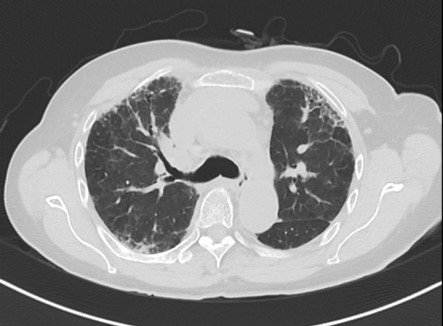

病例2:患者,女,59歲,因“反復(fù)咳嗽、咳痰、氣促8年余”于2024年7月12日求診我院?;颊叨嗄陙矸磸?fù)就診多家醫(yī)院,始終無果。入住我院后經(jīng)多學(xué)科會(huì)診,確診由微生物引起的纖維化型過敏性肺炎。原來患者從事香菇種植工作,歷經(jīng)8年,終于揪出幕后真兇。

病例3:患者,女,73歲,因“咳嗽、氣促5月余”于2024年7月8日求診我院,后確診纖維化型過敏性肺炎,經(jīng)反復(fù)詢問病史和生活情況,過敏原是患者長(zhǎng)期蓋的羽絨被。

過敏原無處不在,但又很隱匿,宿主的易感性也不一樣。過敏性肺炎早發(fā)現(xiàn)、脫離環(huán)境就可以治愈,但是由于患者經(jīng)常未及時(shí)發(fā)現(xiàn)過敏原,對(duì)于早期肺部比較典型的影像特征也缺乏足夠的敏感性,仍繼續(xù)暴露在過敏環(huán)境中,最后發(fā)展成纖維化型過敏性肺炎。我院間質(zhì)肺規(guī)范化診療中心將盡可能詳盡地采集病史以發(fā)現(xiàn)可能存在的環(huán)境暴露因素以及時(shí)間軸關(guān)系,發(fā)揮多學(xué)科診療優(yōu)勢(shì),早發(fā)現(xiàn)早診斷,助力患者盡快脫離過敏原,避免不可逆的肺纖維化。